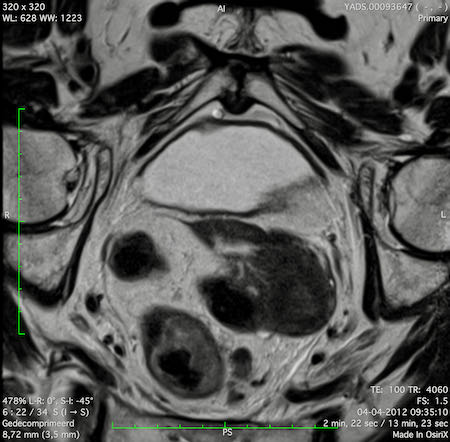

Hình ảnh

Các hình ảnh được cung cấp cho thấy ung thư biểu mô tế bào nhẫn với tình trạng dày lan tỏa thành trực tràng, hình ảnh bia bắn điển hình, và sự xâm lấn mỡ mạc treo trực tràng.